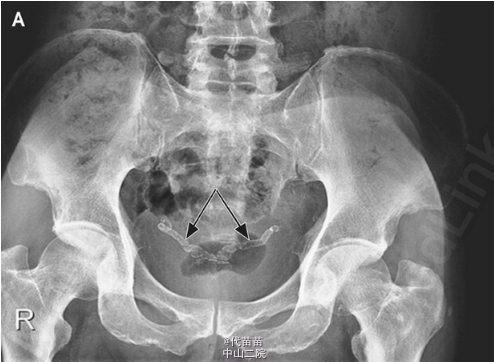

NEJM临床图片:输精管钙化

60岁男性患有晚期糖尿病肾病与甲状旁腺机能亢进,为对其肾结石情况作评估进行放射线检查。结果没发现肾积水或肾结石,但双侧输精管都出现钙化。糖尿病人出现输精管钙化是常见的,可导致不育。此病例并无针对钙化的治疗,只需做好糖尿病和肾病的治疗。